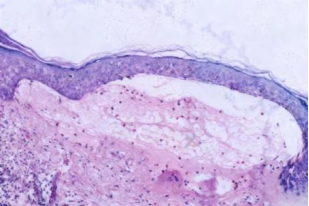

皮损

组织病理检查

(HE× 100)提示:表皮下水疱形成,水疱内可见中性粒细胞、散在嗜酸性粒细胞浸润,真皮浅层血管周围不等量淋巴细胞、中性粒细胞、嗜酸性粒细胞浸润。

图2:皮损组织病理图(HE染色,×100,示表皮下水疱形成)